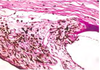

Retina from an adult cat with acquired blindness

Lost photoreceptor and outer nuclear & plexiform layers

Morphologic diagnosis: Retinal atrophy (& degeneration)

Cause:

Enrofloxacin toxicity

histo can’t tell you the etiology

Retina from a horse with increased IOP (glaucoma)

Loss of nerve fiber and ganglion cell layers, but excellent preservation of photoreceptors and outer nuclear layer

MDx: retinal atrophy